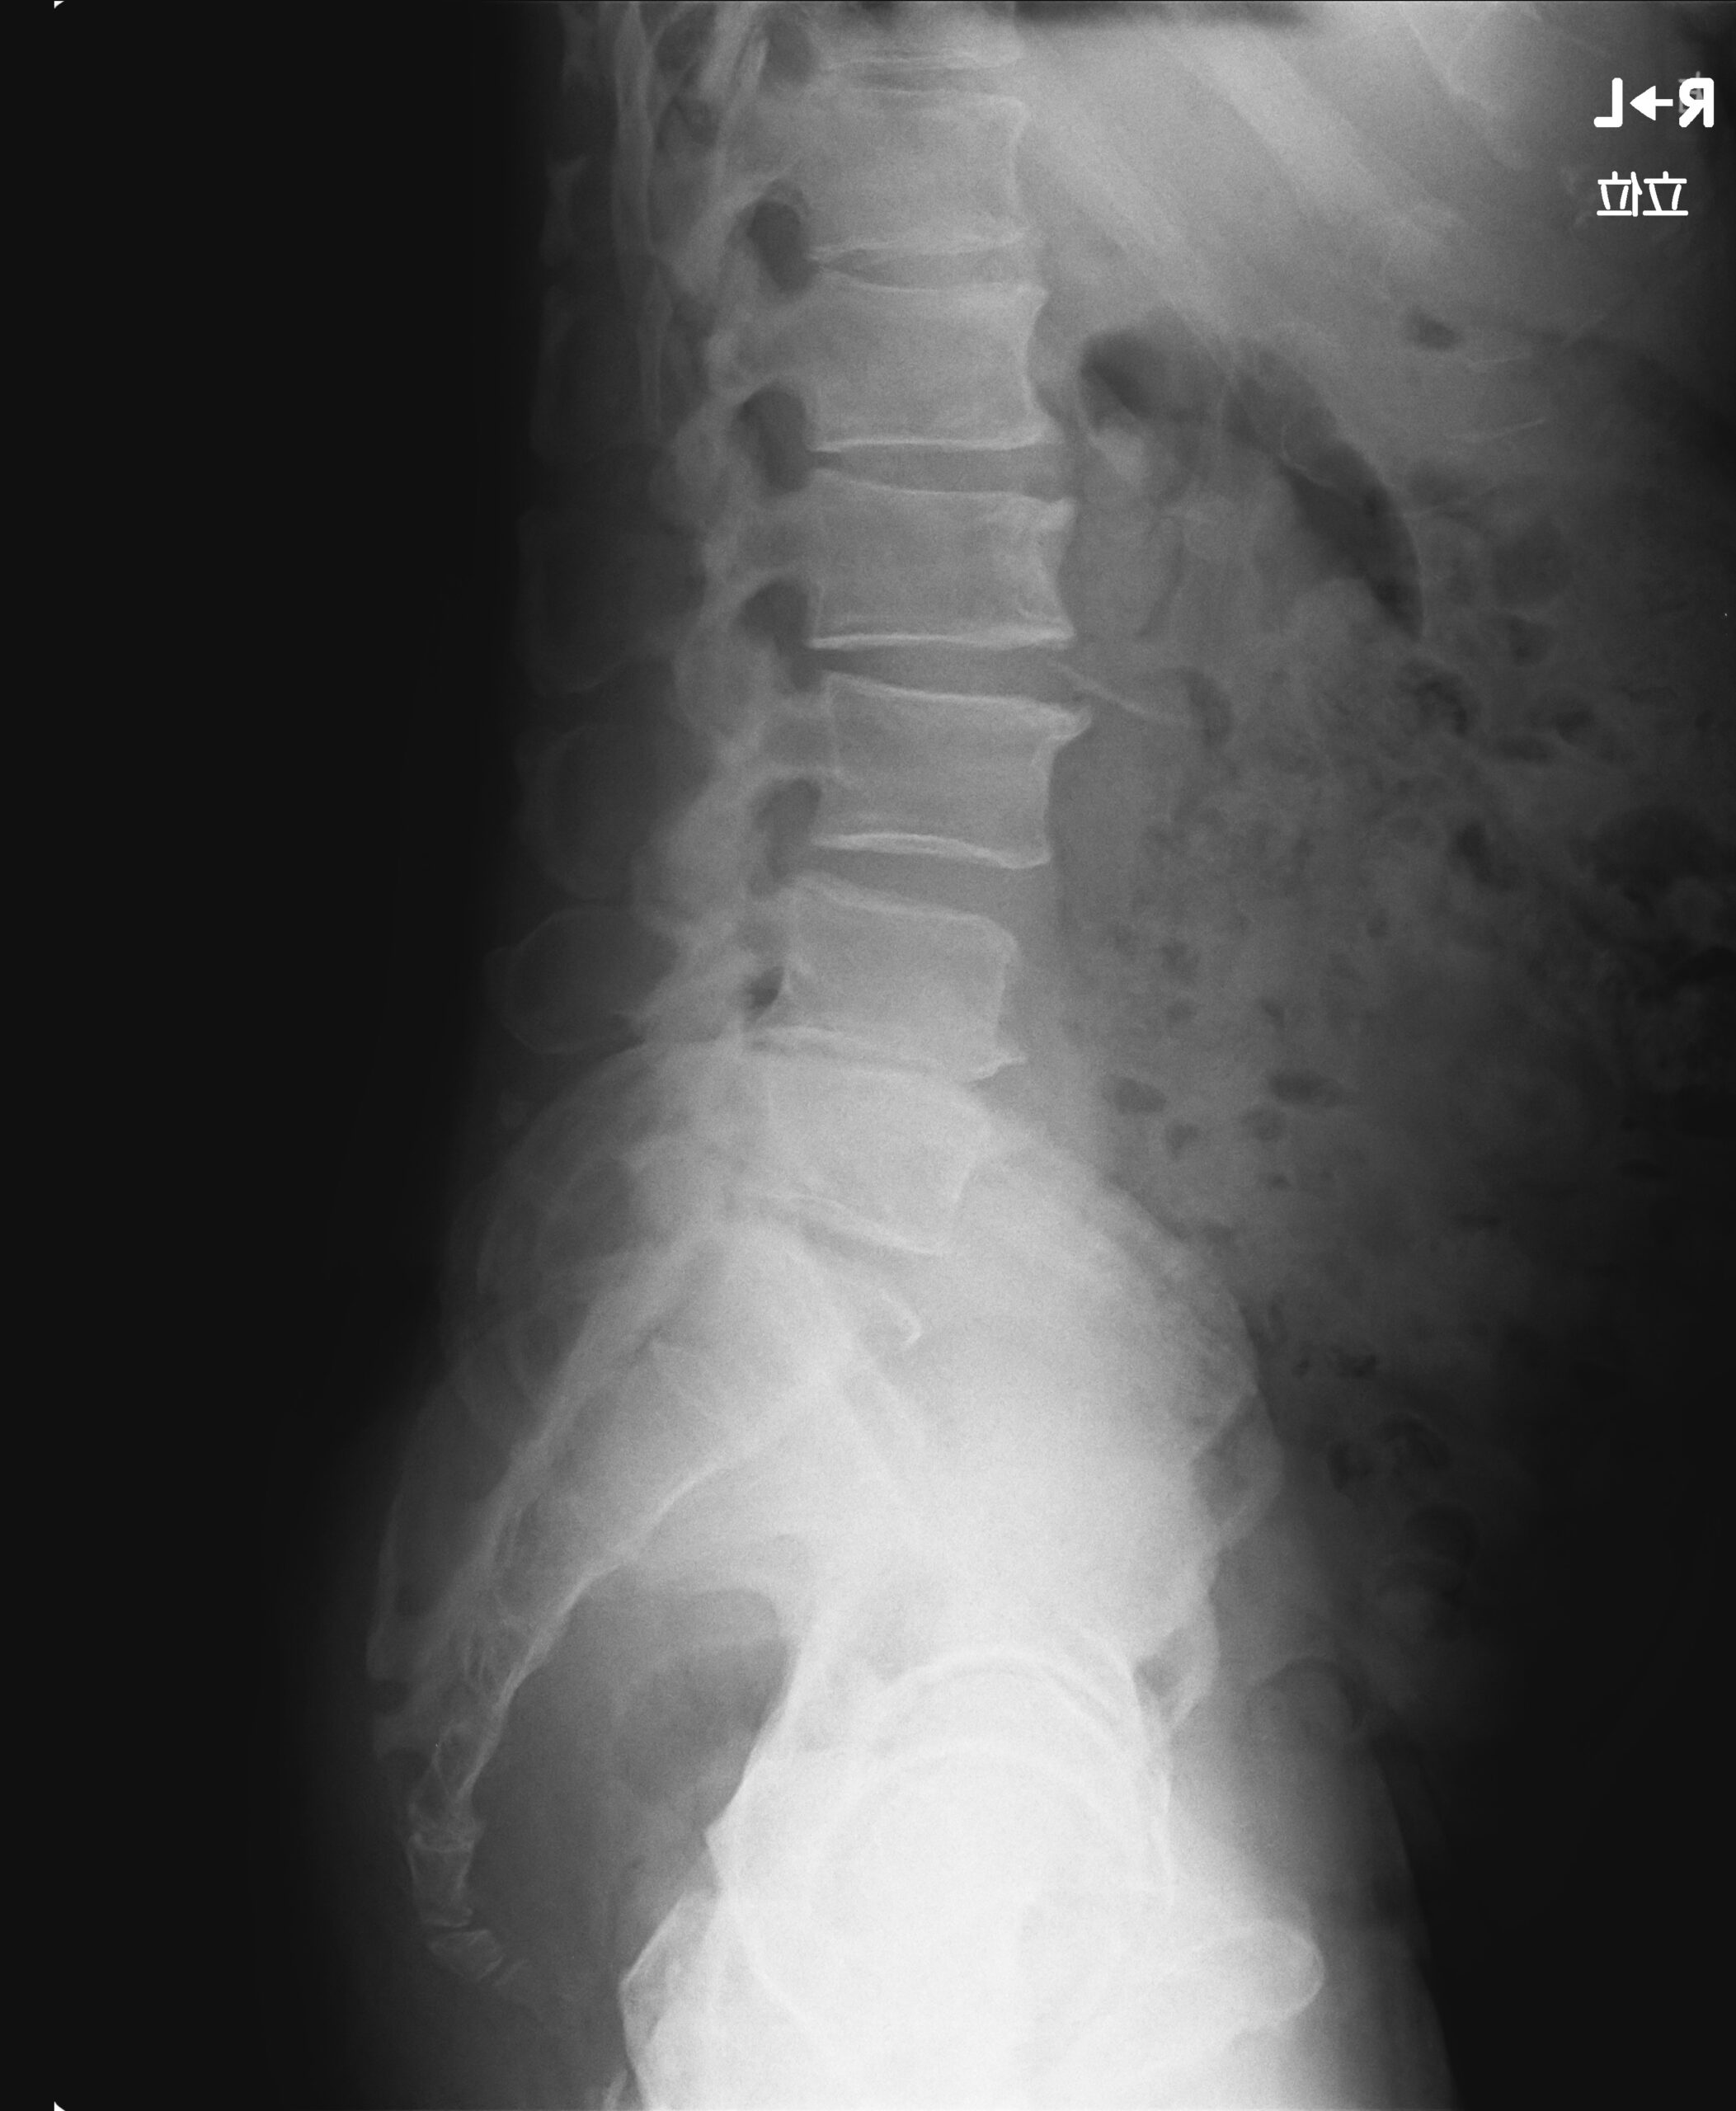

ナーボスコープによる背骨の神経圧迫の検査や立位での骨盤と全ての背骨のレントゲンを見て、原因を特定して施術する当院のことを知り、

腰部、頸部ともに椎間板の段階としてはD3~4レベルだったので週に2回からのケアが理想的だったが、遠方だったことと仕事のスケジュール上週に1回からのケアでスタートすることにした。

今回の患者さんは、上部の首(上部頚椎)と骨盤のいちばん下(仙骨)の両方に神経圧迫(サブラクセーション)が見つかりました。